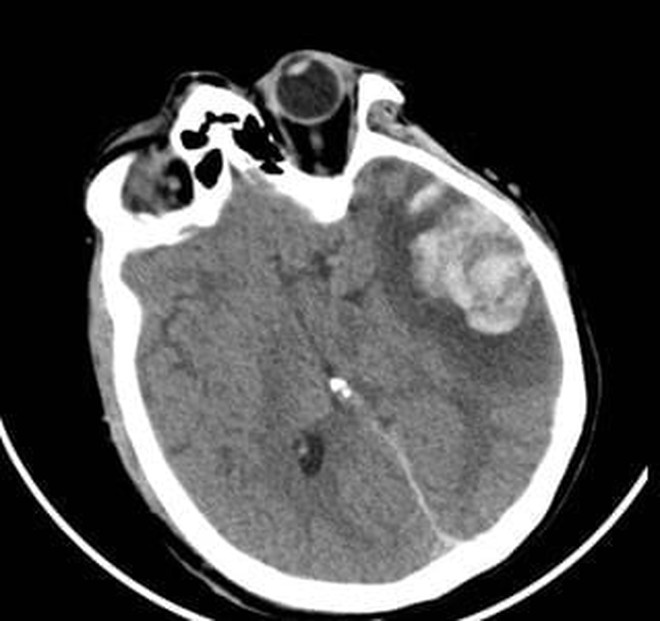

Phim CT não của 2 bệnh nhân

Người mẹ, bà G.N. cũng trong tình trạng rối loạn tri giác, dập não thái dương lượng lớn. Sau hội chẩn kỹ lưỡng, các bác sĩ quyết định lựa chọn phương pháp điều trị bảo tồn nhằm hạn chế tối đa tổn thương thứ phát. Hướng điều trị này cho thấy hiệu quả rõ rệt khi người bệnh dần tỉnh táo, cải thiện khả năng giao tiếp và chức năng ngôn ngữ. Sau 10 ngày điều trị tại Khoa Ngoại thần kinh, bà G.N. hồi phục tốt và được xuất viện.